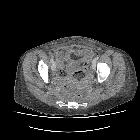

CT

A well-defined "collection" comprised of mixed gas and soft tissue is seen, often surrounded by free fluid and adjacent to other collections. The gas bubbles are arranged in linear patterns, and the collection has a geometric shape. An enhancing margin typical of abscesses is usually not present.